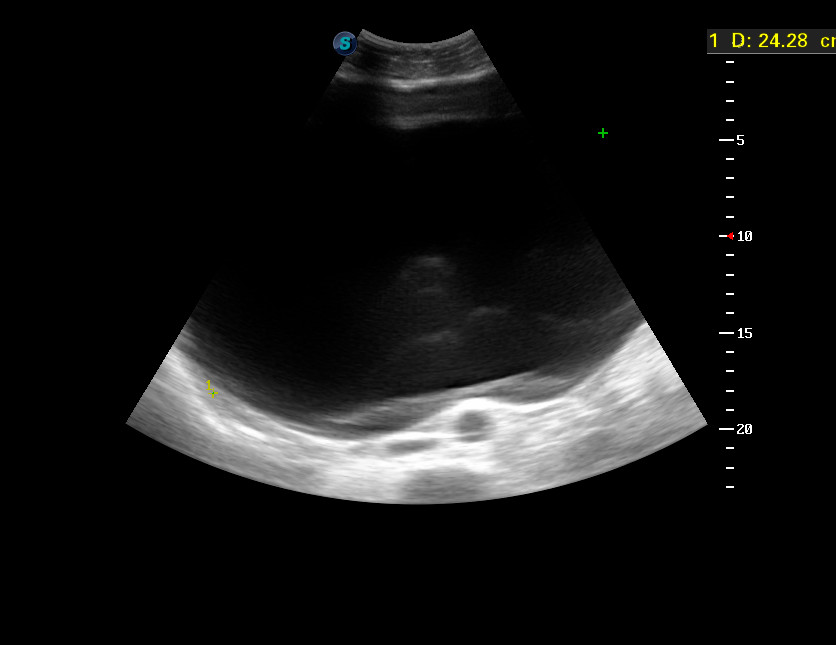

Женщина средних лет с нерезкими болями в животе и его увеличением направлена к гинекологу с подозрением на беременность. Гинеколог отправил на УЗИ исключить кишечную непроходимость.

dec302015130951_0.jpg

dec302015131302_4.jpg

Экстренно отправлена в гинекологическое отделение, где прооперирована.

Д-з: Гигантская киста яичника.

Объем кисты - около 12 литров!

Кстати, если посчитать объем по полученным на УЗИ данным, то получится около 6 литров.

Видимо, измерение по панорамной реконструкции не всегда корректно.